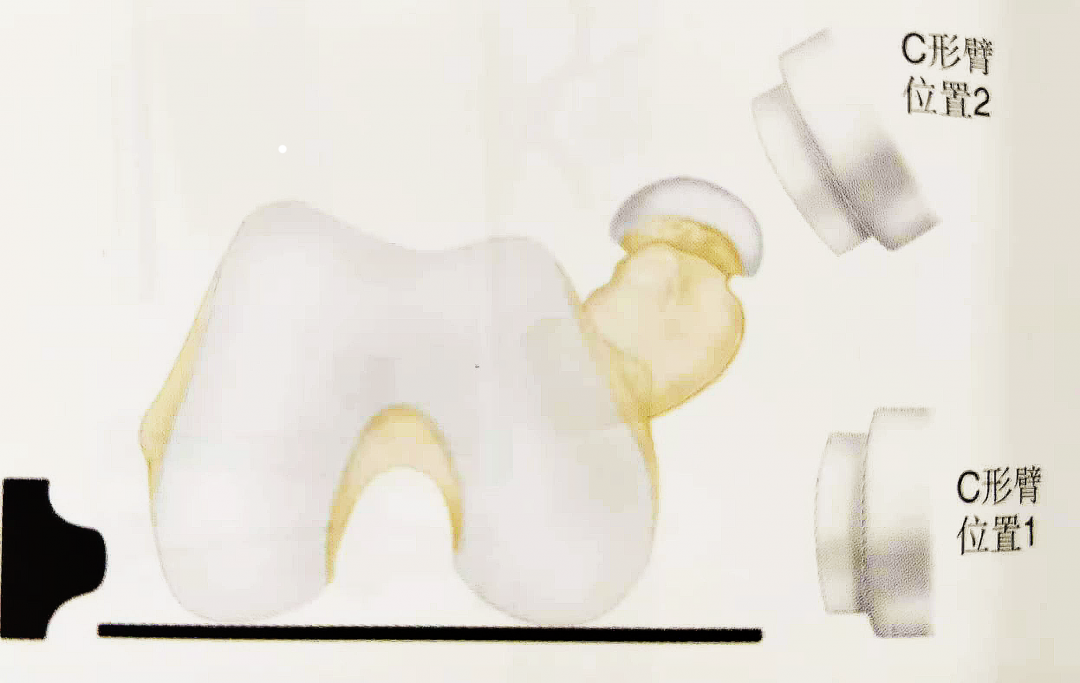

▲ 解剖示意图

• 骨:①大转子;②小转子;③股骨粗线;④内侧股骨矩;⑤前倾角和股骨弓肌。

• 肌肉:①臀中肌;②髂腰肌肌腱;③梨状肌附着处;④股外侧肌;⑤致畸力的影响。

A:肌肉解剖图

B-C:致畸力的影响